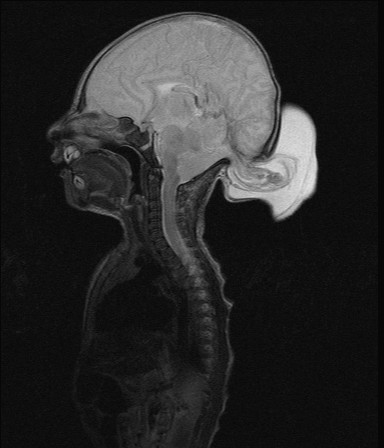

Encephaloceles

Encephaloceles are often grotesque-looking congenital swellings arising from the head or face, that may make childbirth difficult. Child often appears to have a swelling as large as the head. Most of these swellings can be surgically removed successfully.